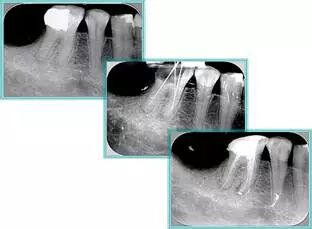

6. 术后 X 线片

术后 X 线片用来评定根管充填 长度、致密度(管壁清晰、侧枝)等指标。

牙胶尖什么颜色【根管治疗】根管治疗的细节把握_https://www.jmylbn.com_新闻资讯_第14张

左图为根管充填术后 X 线片。图中可见,根管充填较好。右下图有白色小点,为侧方加压导致糊剂挤出所致,表明根管充填比较致密。

致密、恰到好处的充填可去除干净根管里感染灶,机体逐渐恢复。

牙胶尖什么颜色【根管治疗】根管治疗的细节把握_https://www.jmylbn.com_新闻资讯_第15张

多根牙时候需进行偏移投照,正位投照无法说明具体哪根牙根管充填效果。        二、根管预备及充填要求